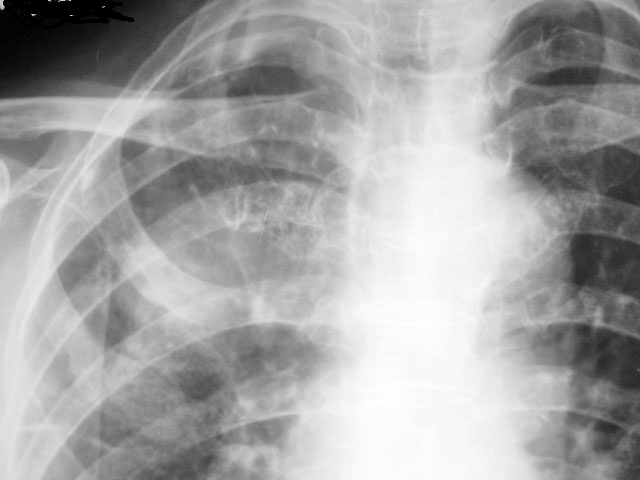

以下是引用随光逐影在2010-4-4 17:47:00的发言:[br]右上肺肿块,不排除肿瘤性病变;建议行ct扫描检查。

以下是引用zxl51642在2010-4-4 15:11:00的发言:[br]做ct看看.